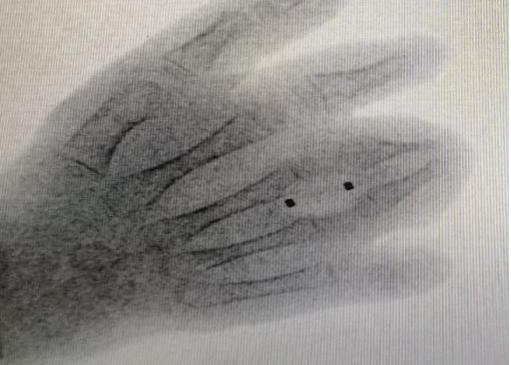

球囊扩张技术是用一个微创的办法,在手背侧把球囊完全置入到部分融合的指骨和瘢痕皮肤之间,用球囊扩撑,循序渐进把手指头撑开,方便后期做皮肤分离。

骨性并指撑开效果